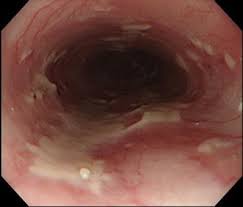

Unlike herpes esophagitis, cmv esophagitis almost never occurs in immunocompetent patients, and the vast majority of affected individuals are found to have aids. Clinical effect of itopride hydrochloride on the digestive symptoms of chronic gastritis with reflux esophagitis // clin. Causes of esophagitis include stomach acids backing up into the esophagus treatment for esophagitis depends on the underlying cause and the severity of tissue damage. Evaluation and management of infectious esophagitis in immunocompromised and immunocompetent individuals. „ odynophagia is the predominant presenting symptom. Cobblestone esophagitis (эзофагит со слизистой булыжной мостовой). If left untreated, esophagitis can damage the lining of the. It can arise from a range of causes which include:

Definition cmv esophagitis is an infection of the esophagus caused by the cytomegalovirus (cmv). The endoscopic findings in hsv esophagitis vary with the interval between esophageal infection and endoscopic examination. If left untreated, esophagitis can damage the lining of the. Clinical effect of itopride hydrochloride on the digestive symptoms of chronic gastritis with reflux esophagitis // clin. A clinical case in a child was given. The aims of this study were to investigate the implications of the endoscopic findings for the. Cytomegalovirus esophagitis is a form of esophagitis associated with cytomegalovirus. Causes of esophagitis include stomach acids backing up into the esophagus treatment for esophagitis depends on the underlying cause and the severity of tissue damage. Comorbid occurrence of laryngeal or pulmonary disease with esophagitis in united states military veterans // gastroenterology. Videoradiography with lateral/ap views are the optimal studies. Esophagitis can cause painful, difficult swallowing and chest pain. As the practice shows, hypodiagnostics of eosinophilic esophagitis and other eosinophilic gastrointestinal diseases takes place. Eosinophilic esophagitis attributed to gastroesophageal re.

If left untreated, esophagitis can damage the lining of the. Definition cmv esophagitis is an infection of the esophagus caused by the cytomegalovirus (cmv). Inoue k., sanada y., fijimura j., mihara o. Epidemiology and infectious complications of human immunodeficiency virus antibody positive patients. This condition occurs in the setting of patients with a weakened immune system who are susceptible. Densely matted pseudohyphae and budding spores in squamous debris, fibrinopurulent exudate or necrotic debris. A clinical case in a child was given. Associated with cmv or hsv esophagitis in immunocompromised (see case reports below); Cobblestone esophagitis (эзофагит со слизистой булыжной мостовой). „ odynophagia is the predominant presenting symptom. Esophagitis refers to inflammation of the esophagus. Causes of esophagitis include stomach acids backing up into the esophagus treatment for esophagitis depends on the underlying cause and the severity of tissue damage. Congenital esophageal stenosis, corrugated ringed esophagus, and eosinophilic esophagitis.